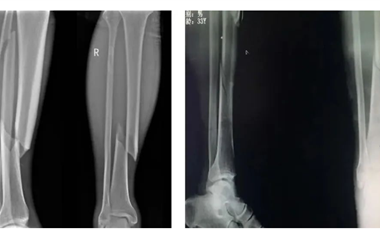

掌骨(gu)(gu)(gu)骨(gu)(gu)(gu)折是(shi)手部常見(jian)骨(gu)(gu)(gu)折之(zhi)一,多為直接暴力引起。由(you)于(yu)骨(gu)(gu)(gu)間肌(ji)、蚓狀肌(ji)和屈(qu)指肌(ji)的(de)牽拉(la),骨(gu)(gu)(gu)折端向背(bei)側成角。依據外傷史,手背(bei)腫脹、疼痛(tong)、畸(ji)形(xing)、局(ju)部壓(ya)痛(tong)等(deng)表(biao)現,結合X線片檢查(cha)診(zhen)斷可確診(zhen)。